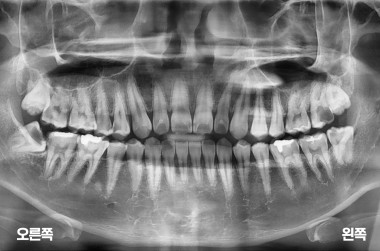

아래 양쪽 사랑니 발치

MORE